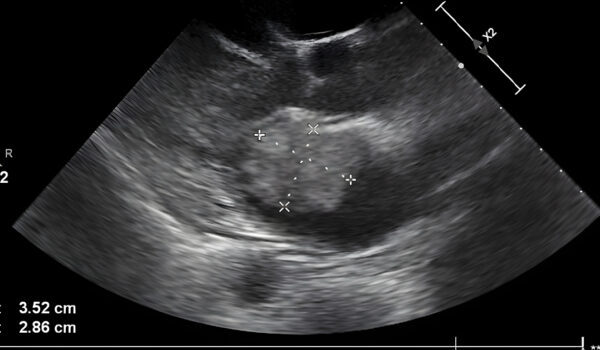

Medical scans revealed an aortic septum abnormality, a rare condition that could threaten Kyler’s life if not closely monitored. Amanda’s anxiety grew, prompting her to rely heavily on prayer for comfort and guidance during the pregnancy.

During the appointment, Bailey noticed something unusual in the ultrasound image. She asked her mother whose hand appeared to be cradling the baby’s head, prompting Amanda to examine the image closely herself with a mixture of shock and awe.

Amanda shared the image on Facebook, describing it as showing the divine presence of a hand gently holding her son’s head. She expressed profound gratitude for what she perceived as God’s protective touch over Kyler.

In her post, Amanda wrote, “In one of his pictures it has the appearance of a hand holding his head,” adding that the sight brought her to tears, reflecting on all God has done for her family.

Medical professionals caution that while unusual shapes may appear in ultrasound images, Amanda’s interpretation is a personal and meaningful reflection of her faith and emotional journey throughout pregnancy.